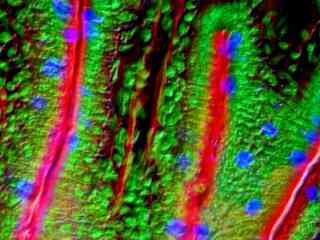

Fluorescence Microscopy

The widefield reflected light fluorescence microscope has been a fundamental tool for the examination of fluorescently labeled cells and tissues since the introduction of the dichromatic mirror in the late 1940s. Furthermore, advances in synthetic fluorophore design coupled to the vast array of commercially available primary and secondary antibodies have provided the biologist with a powerful arsenal in which to probe the minute structural details of living organisms with this technique. In the late twentieth century, the discovery and directed mutagenesis of fluorescent proteins added to the cadre of tools and created an avenue for scientists to probe the dynamics of living cells in culture. This gallery examines the fluorescence microscopy of both cells and tissues with a wide spectrum of fluorescent probes.

Rat Sections

The humble rat has had an outsized impact on human history. In the Middle Ages, the black rat (Rattus rattus) was blamed for spreading the Black Plague through its fleas, a pandemic that killed a third of Europe's population, an estimated 34 million people. In modern times, however, a larger cousin, the Brown rat (Rattus norvegicus) has become an important model organism in biological research. Selective breeding of the Brown Rat has produced the albino laboratory rat. Rats grow quickly to sexual maturity and are easy to keep and breed in captivity.